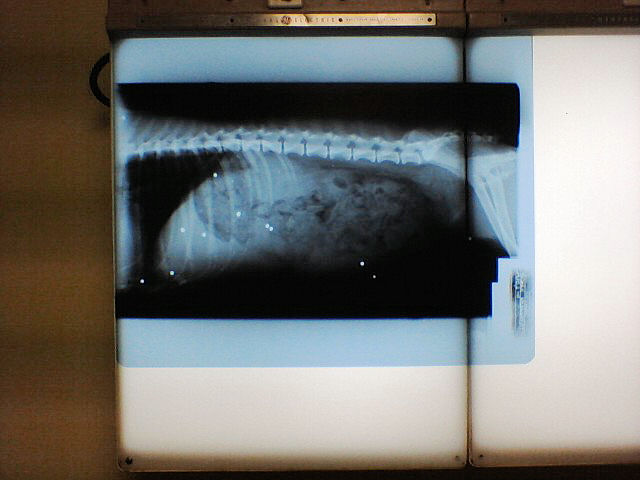

Wendy has a bladder infection and had to go to the vet to get checked out today.

Wendy is a very lucky girl to be with you. How awful that she was shot.

We call those white dots “Mississippi Microchips”